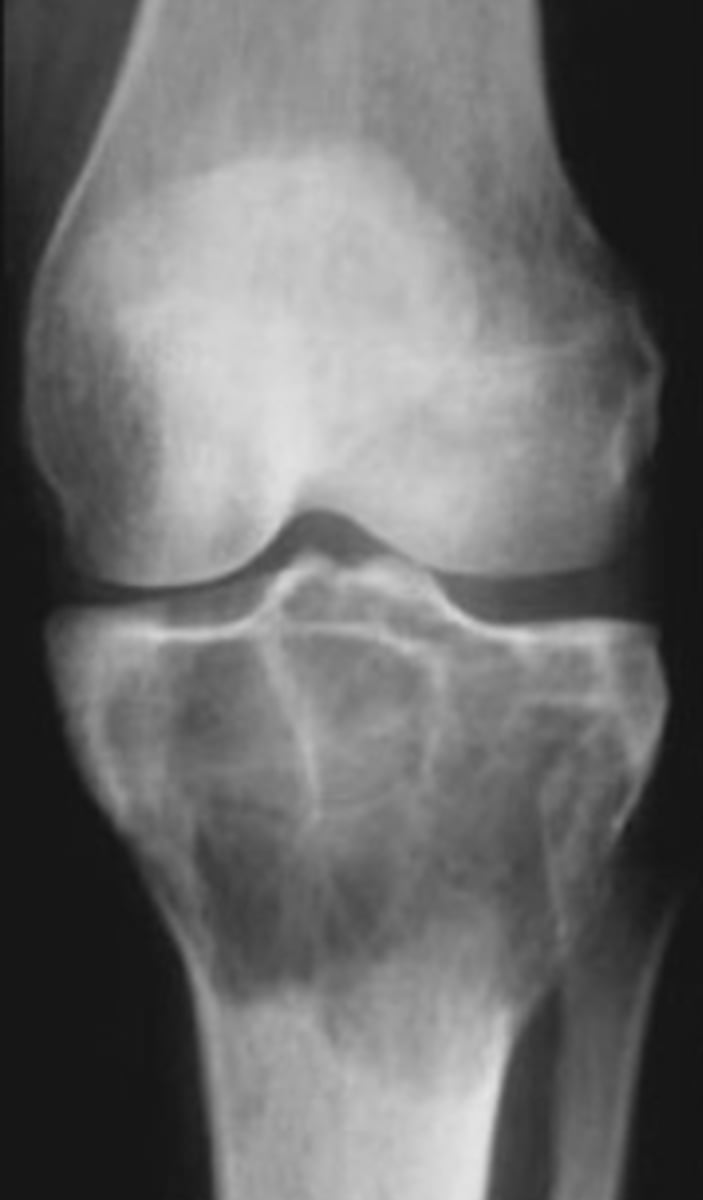

- Osteolytic

- Geographic

- Multiloculated and septated

- Begin in metaphysis

- Extend to subarticular bone

- Expansion

- Eccentric

- Quasi-malignant (can't tell benign from malignant)

State the imaging features of giant cell tumor

<p>State the imaging features of giant cell tumor</p>